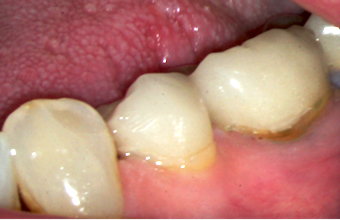

In my opinion, the best areas to consider repairing are the buccal and lingual margins because they allow access to physically remove the decay and the opportunity to visually confirm success. However, just because you can’t see any more decay doesn’t mean that there isn’t additional decay under the crown.

Testing the seal of bonded restorations is really simple. After preparing the area I want to repair, I simply place Sable Seek from Ultradent in the preparation as pictured above. After letting the Sable Seek sit for at least 10 seconds, I simply wash it away. If you have a good seal, it will all rinse out, but if you don’t, you’ll see a line of residual Sable Seek.